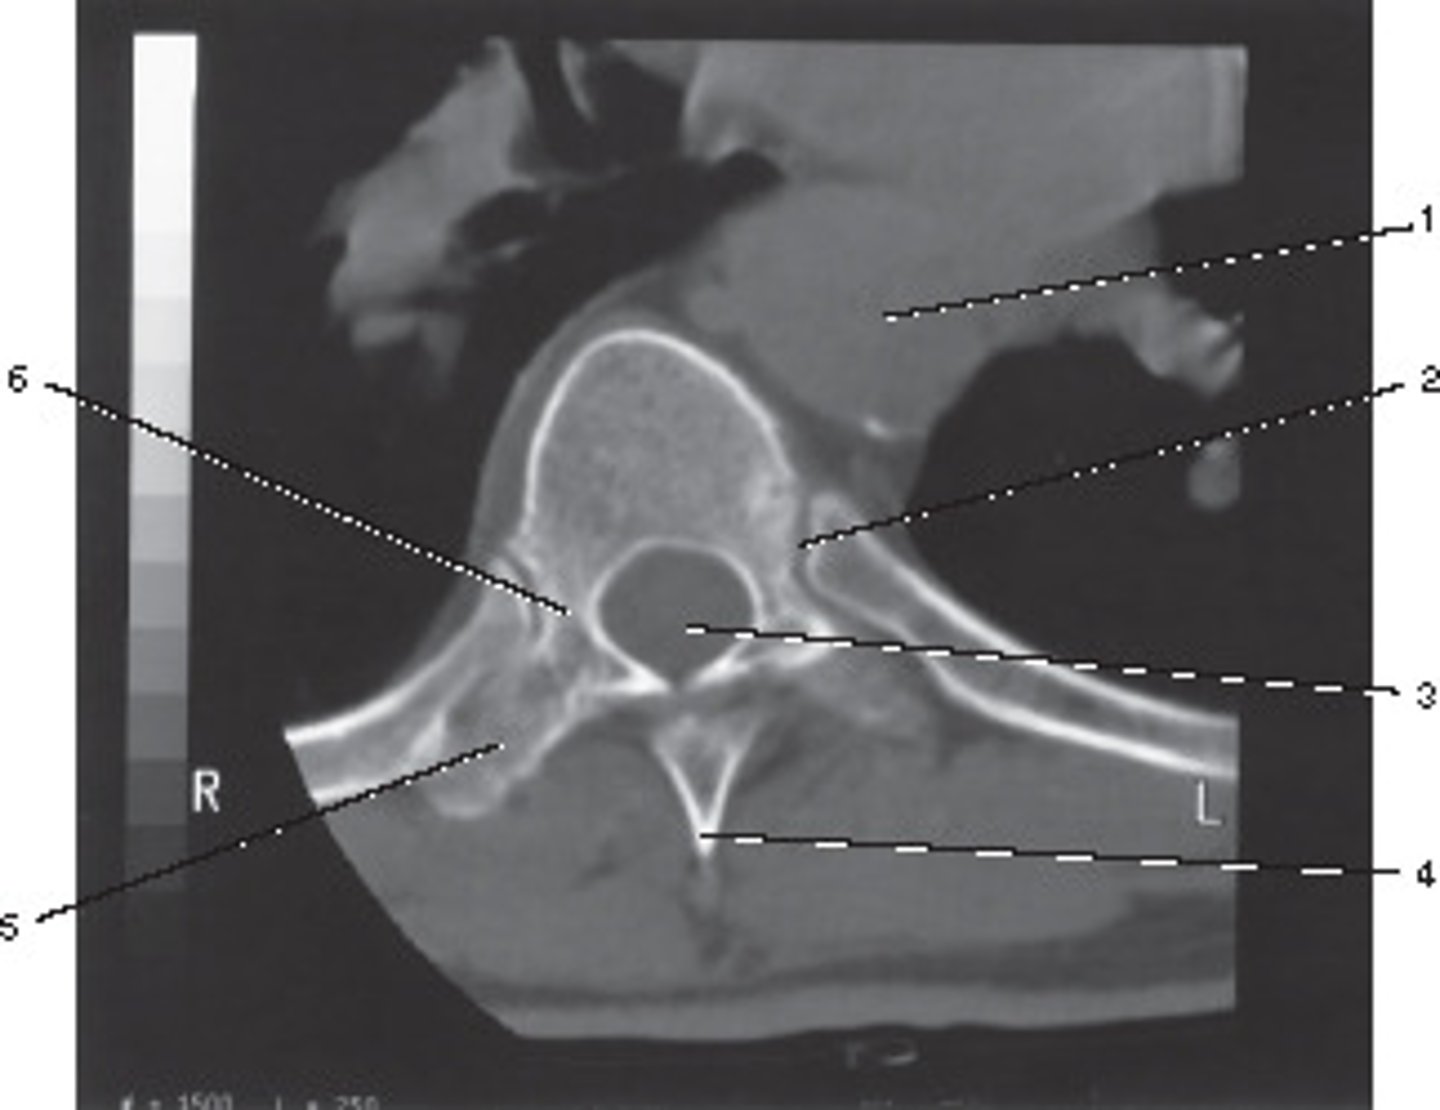

Pedicle

Number 6 corresponds to which of the following?

<p>Number 6 corresponds to which of the following?</p>

Vertebral Artery

Number 3 corresponds to which of the following?

<p>Number 3 corresponds to which of the following?</p>

High Spatial Frequency

What type of algorithm would be best suited to demonstrate the bony details of this shoulder?

<p>What type of algorithm would be best suited to demonstrate the bony details of this shoulder?</p>